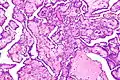

Histology

Cancer cells have distinguishing histological features visible under the microscope. The nucleus is often large and irregular, and the cytoplasm may also display abnormalities.[3]

Nucleus

The shape, size, protein composition, and texture of the nucleus are often altered in malignant cells. The nucleus may acquire grooves, folds or indentations, chromatin may aggregate or disperse, and the nucleolus can become enlarged. In normal cells, the nucleus is often round or solid in shape, but in cancer cells the outline is often irregular. Different combinations of abnormalities are characteristic of different cancer types, to the extent that nuclear appearance can be used as a marker in cancer diagnostics and staging.[4]